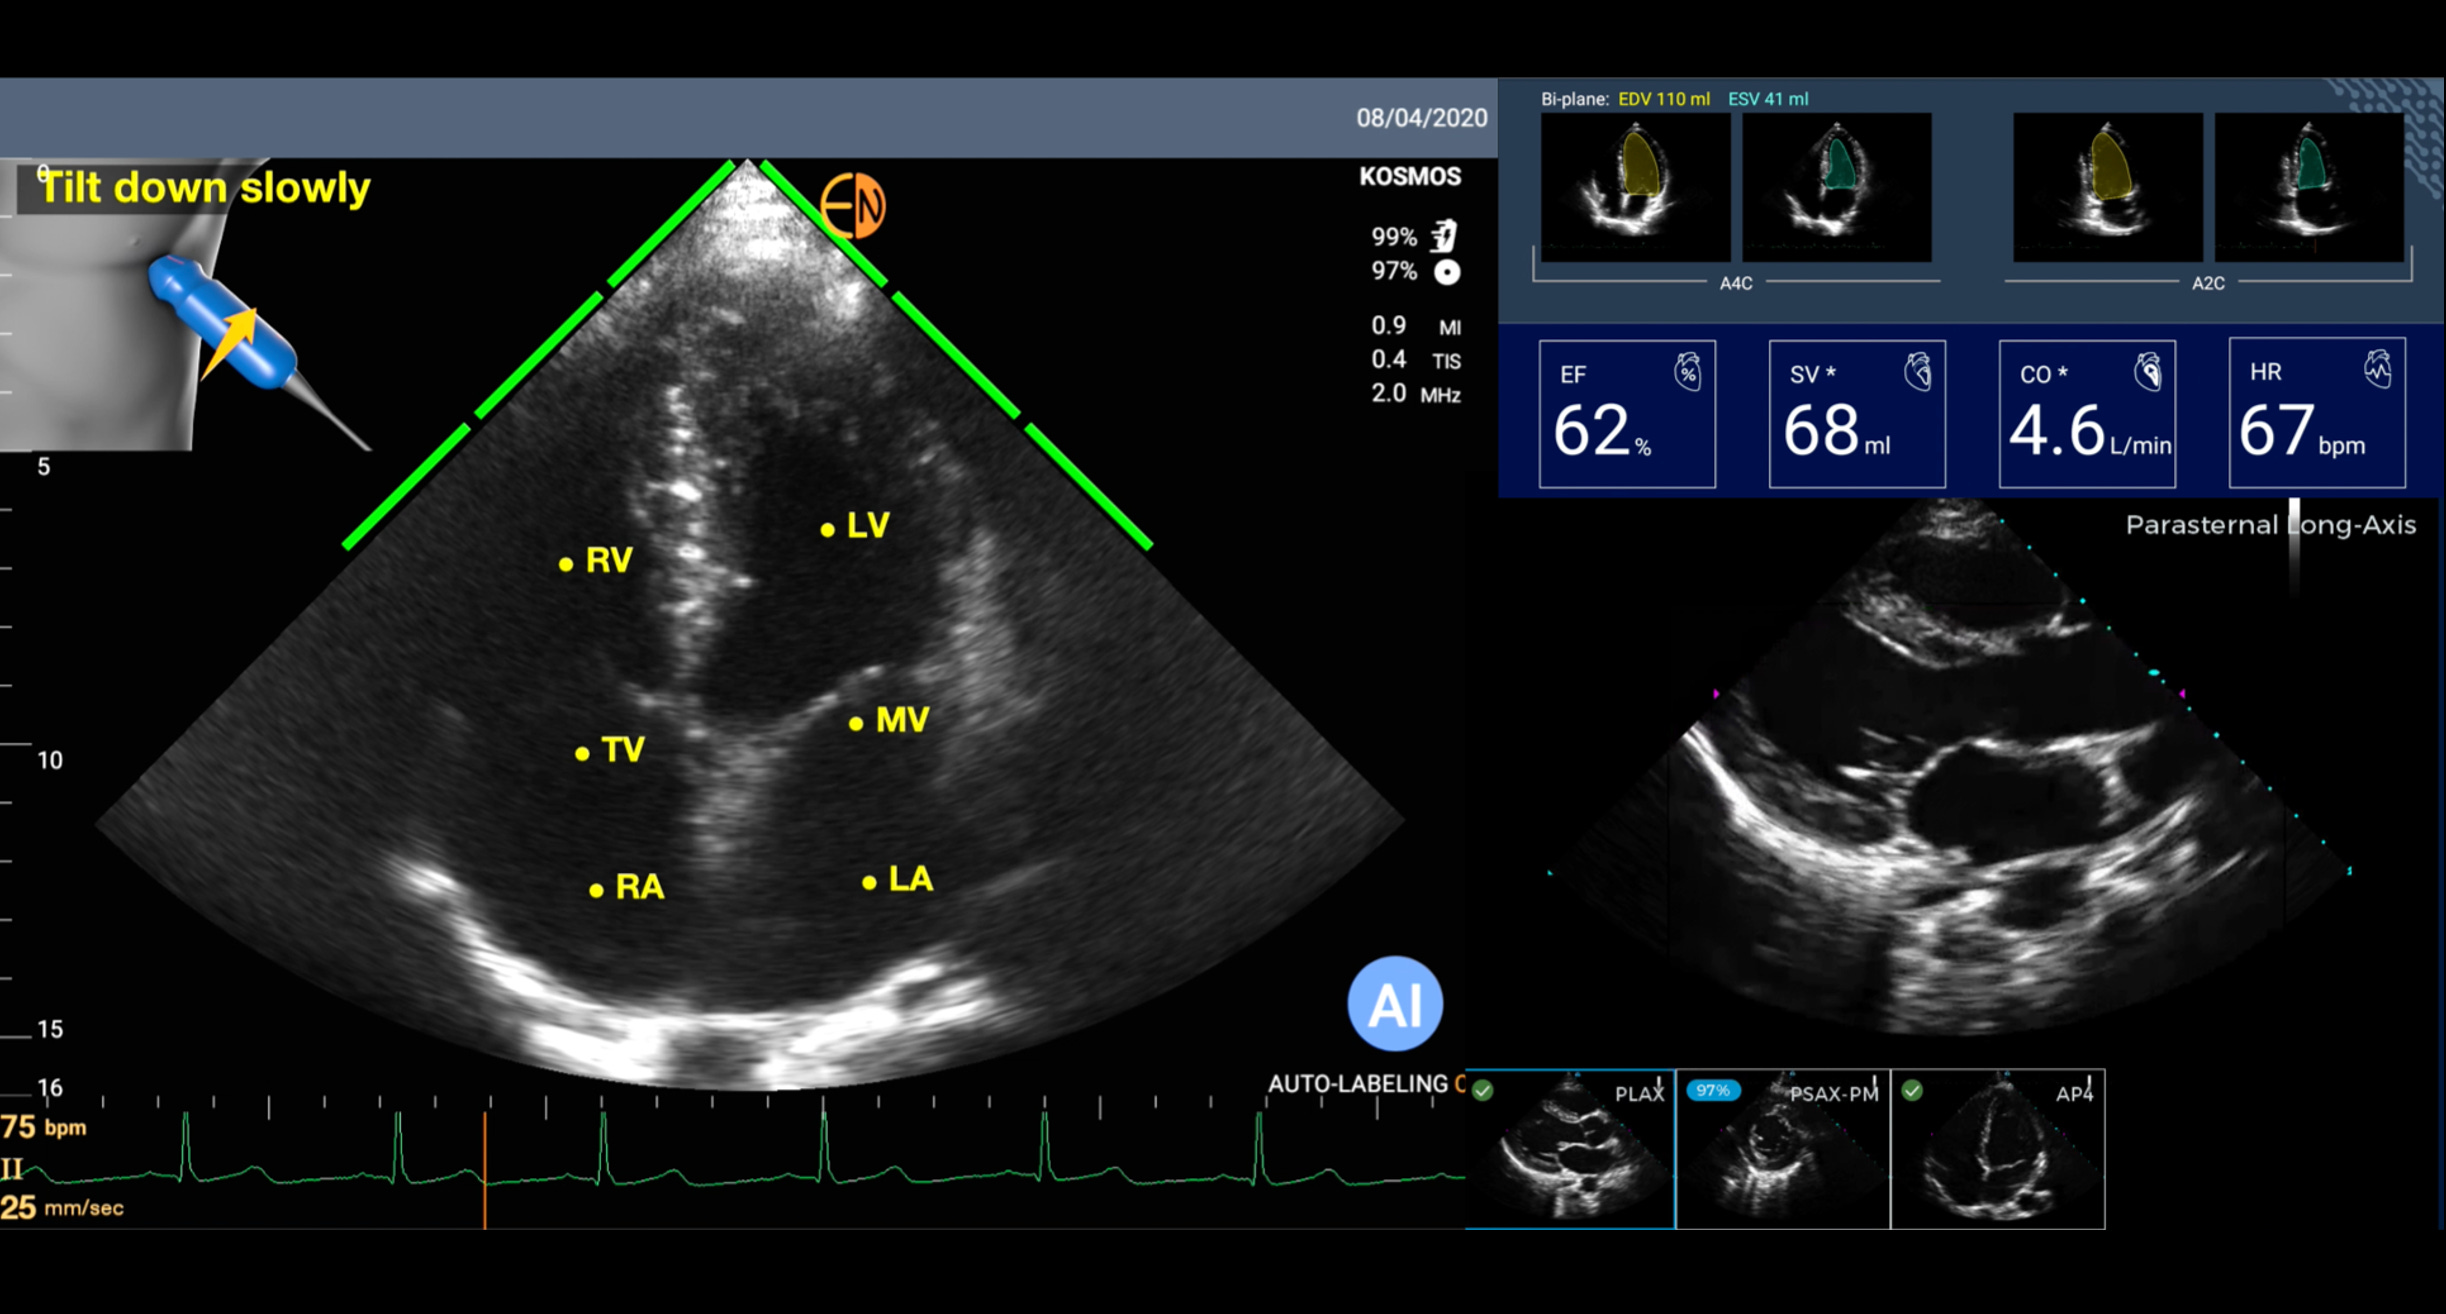

But now with A.I. that has changed. For the heart, there are a number of AI tools that will guide a person with no echocardiographic knowledge for acquiring images or interpreting them. All that is needed is for a person to put the smartphone probe on the left side of the chest. Then the AI can tell the person to move it up or down, or clock, or counterclockwise, until it “sees” the heart image and automatically captures it a short video loop. And then automatically labels the structures and provides an interpretation. This sets up the potential for anyone to perform a screening echocardiogram and get an initial reading of it. An example is shown below with automated labeling (LV=left ventricle, LA=left atrium, MV=mitral valve) and providing the ejection fraction (EF%) and other outputs. If this can be done with the heart, the most challenging organ to image because of its motion, you can imagine how much easier it would be for many other organs when just a static shot is needed (like the kidney photo above).